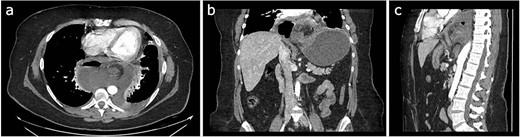

Initial treatment included intravenous crystalloid fluid repositioning, pain management, and antibiotic therapy. After diagnosing perforated gastric volvulus on a computed tomography (CT) scan, a diagnostic laparoscopy was performed. A hiatal hernia was identified with protrusion and twisting of the gastric body (Fig. 2). As the stomach body was reduced back to the abdominal cavity, a 1.5-cm perforation at the level of the greater curvature was detected. It was primarily sutured and covered with an omental patch (Fig. 3). The ischemic hernia sac containing the stomach was filled with food scraps and resected (Fig. 4). Laparotomy conversion was necessary due to hemodynamic instability attributable to the laparoscopic pneumoperitoneum. A 180° anterior fundoplication of the stomach (Dor’s Technic) associated with diaphragmatic raffia was performed. Gastric air leak testing was negative and intraoperative endoscopy showed no other defects on the gastric wall.

Twisted stomach body protruding through the diaphragmatic pillars, laparoscopic view.